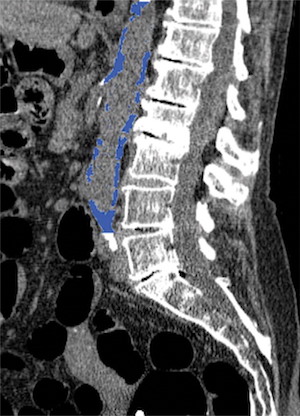

Dans le cadre de cette nouvelle étude, les chercheurs ont évalué la relation entre la calcification aortique abdominale identifiée par scanner et les événements cardiovasculaires survenus chez 829 patients asymptomatiques âgés en moyenne de 58 ans environ. Les patients avaient subi une coloscopie virtuelle de dépistage entre avril 2004 et mars 2005. Ils ont été en mesure de suivre les patients pendant 11 ans en moyenne pour voir s’ils avaient développé des événements cardiovasculaires indésirables tels qu'une crise cardiaque, un accident vasculaire cérébral, une insuffisance cardiaque congestive, voire un décès.

Sur les 829 patients, 156 (18,8%) ont fait l'objet d'un événement cardiovasculaire majeur. Les événements sont survenus près de sept ans après le scanner, en moyenne, et se sont matérialisés par une crise cardiaque chez 39 personnes et un décès chez 79 personnes. La calcification aortique abdominale identifiée par scanner a ainsi joué le rôle d'un puissant facteur prédictif d'événements cardiovasculaires futurs, surpassant le score de risque de Framingham. La calcification aortique abdominale était en moyenne cinq fois plus élevée chez les personnes ayant eu un événement cardiovasculaire que chez celles qui n’en avaient pas eu.

Sur les 829 patients, 156 (18,8%) ont fait l'objet d'un événement cardiovasculaire majeur. Les événements sont survenus près de sept ans après le scanner, en moyenne, et se sont matérialisés par une crise cardiaque chez 39 personnes et un décès chez 79 personnes. La calcification aortique abdominale identifiée par scanner a ainsi joué le rôle d'un puissant facteur prédictif d'événements cardiovasculaires futurs, surpassant le score de risque de Framingham. La calcification aortique abdominale était en moyenne cinq fois plus élevée chez les personnes ayant eu un événement cardiovasculaire que chez celles qui n’en avaient pas eu.

Les résultats soulignent le potentiel de l'évaluation calcique de l'aorte abdominale en tant qu'outil de dépistage supplémentaire n'augmentant pas le temps d'exploration ni de dose de rayonnement. Les patients pourraient ainsi être soumis à des schémas thérapeutiques préventifs en fonction de leur catégorie de risque cardiovasculaire. "Des milliers de tomodensitométries sont effectuées chaque jour aux États-Unis, poursuit le Dr O’Connor. Si un patient passe un scanner pour cholécystite, par exemple, et que nous y identifions une calcification aortique abdominale, nous pouvons alors avoir à faire à un patient sujet à un événement cardiovasculaire prochain."